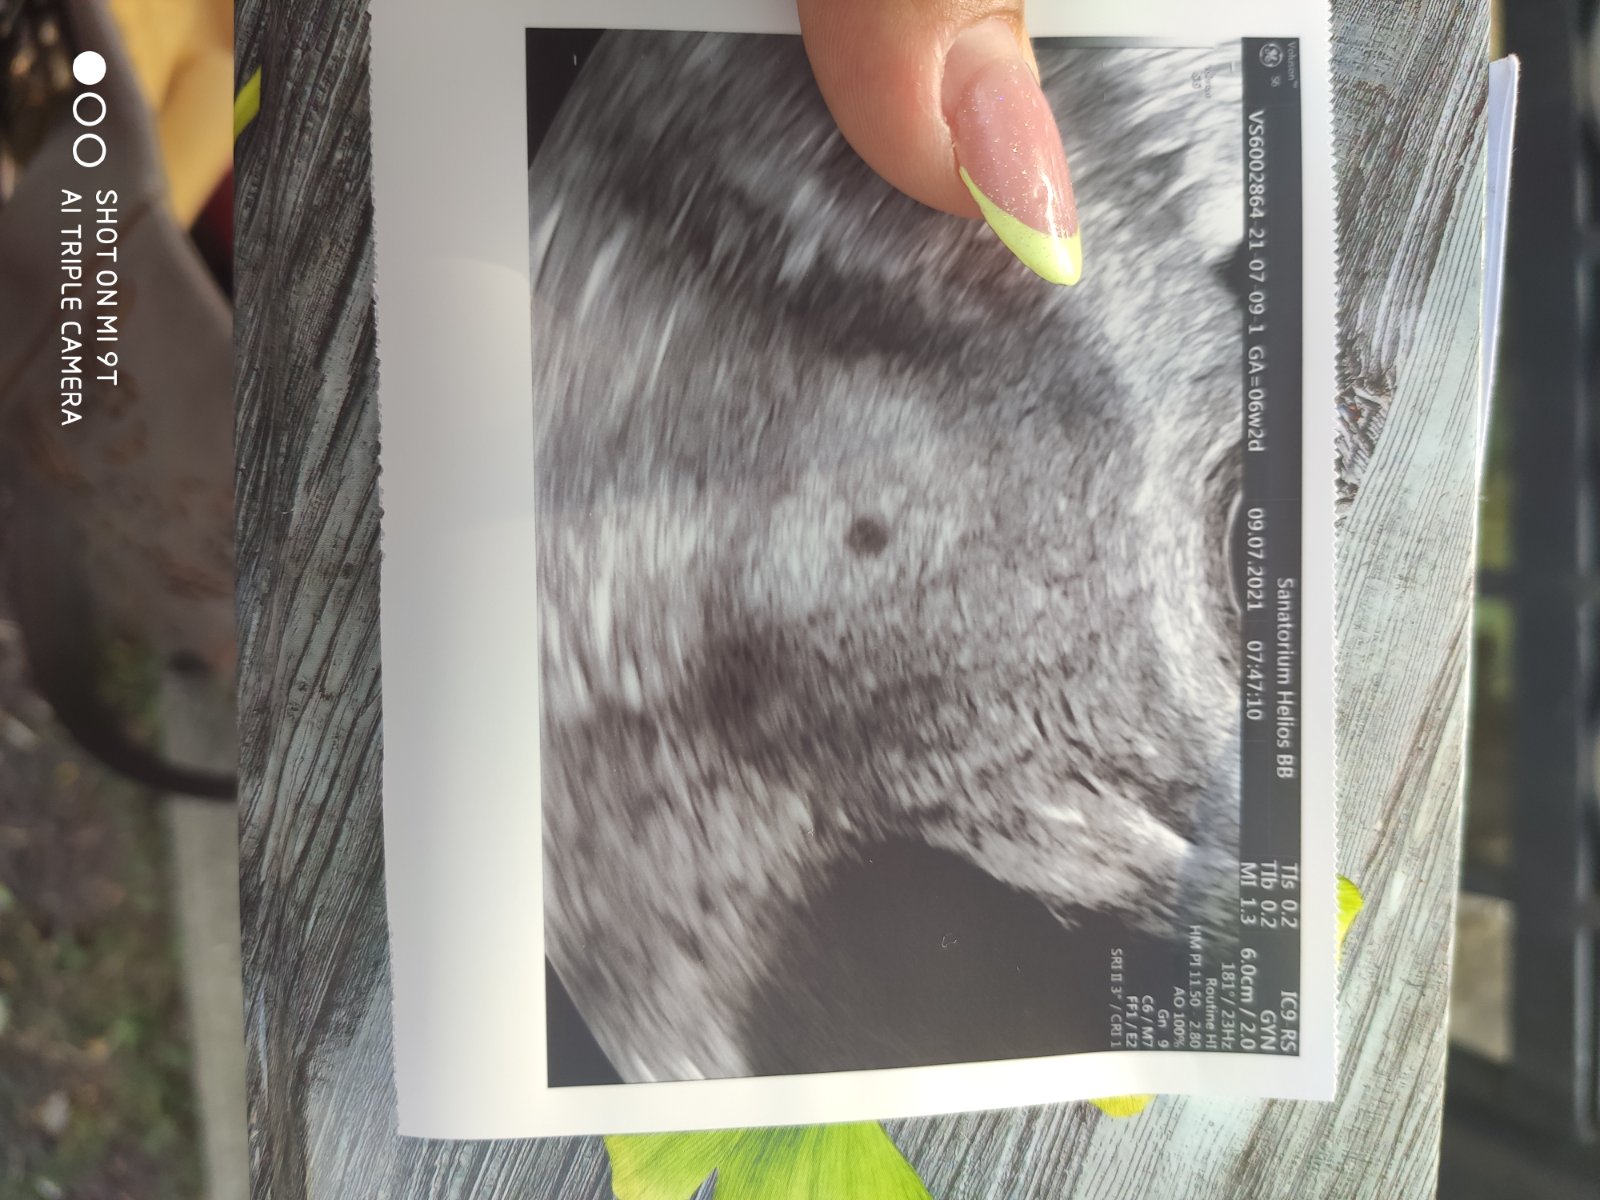

autorDievčatá naša malá bodka, gestacny vak🙏😍😍🙏😀😀😀🙏😀😀😀

autorDievčatá hcg 1055 hodnota 😍😍😍🥰🥰🥰🥰